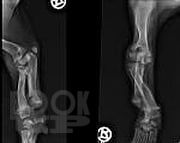

В учебном пособии подробно освещены вопросы эмбриогенеза трубчатых костей, нарушения их развития и формирования, дана подробная классификация нарушений дизонтогенеза. Описаны основные нозологические формы дизонтогенетических нарушений, наблюдаемых в клинической практике. Освещены вопросы кровоснабжения длинных трубчатых костей и репаративной регенерации при их переломах.